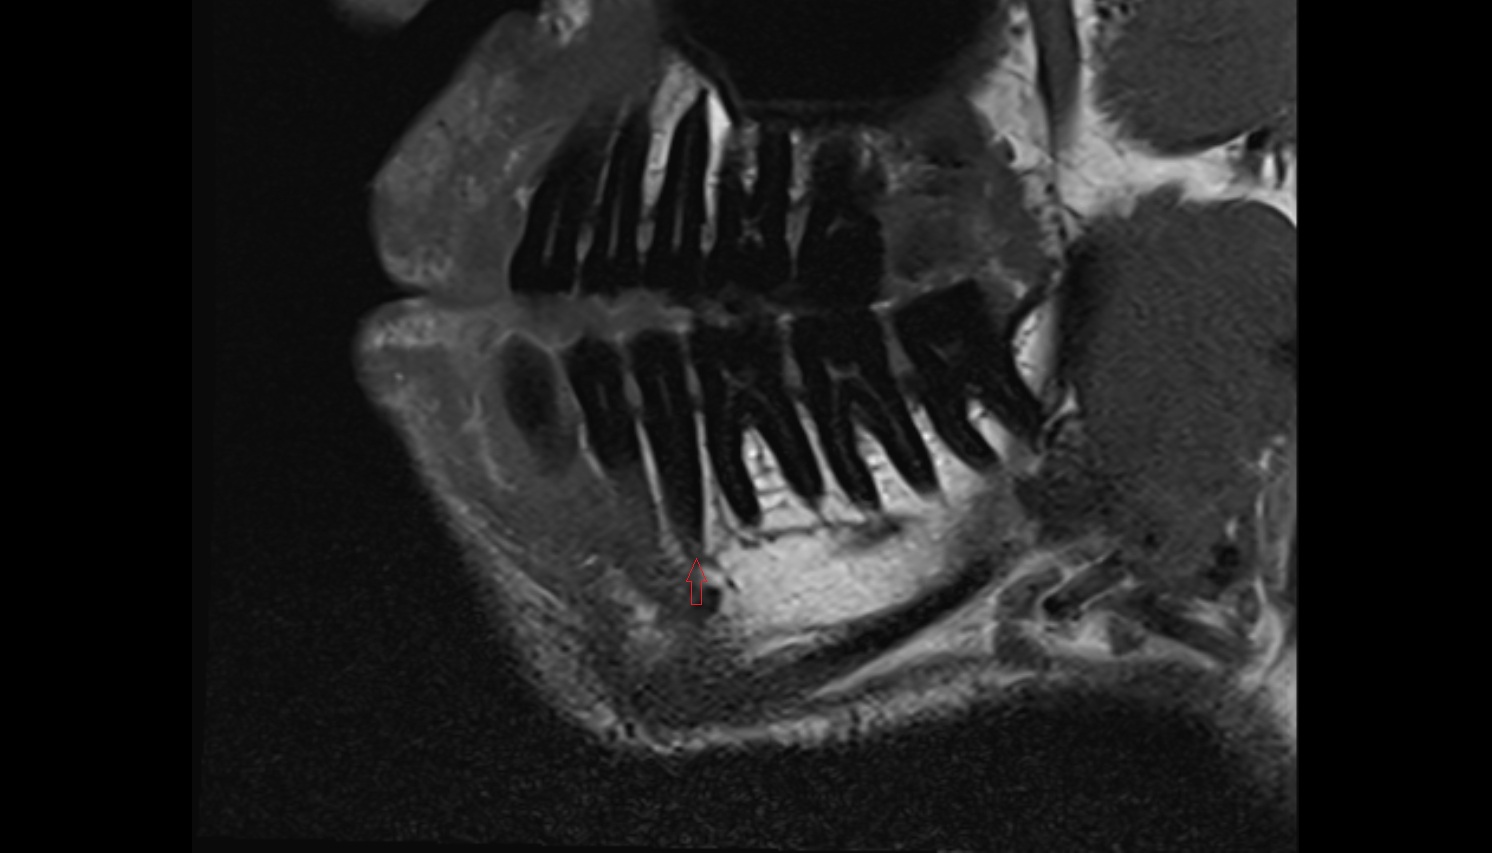

- Mandibular canal

- inferior alveolar artery

- Inferior alveolar nerve

- Root of lower molar tooth

- Lower molar apical foramen

- Dental branches of inferior alveolar artery, vein, & nerve